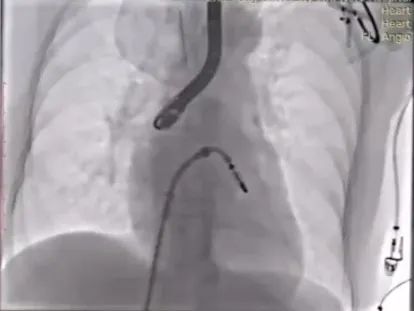

手术操作

术中观测,卵圆窝范围较小,解剖位置偏下偏前;即便选择其最靠后的位置进行穿刺,穿刺高度仍受限制。

但鉴于肌部组织较厚,穿刺难度较大,且存在较高的医源性损伤风险,同时经肌部穿刺更易引发Aortic Hugger现象,增加术中并发风险,因此最终仍选择从卵圆窝进行穿刺操作。

最终穿刺高度受限,仅3.3cm

穿刺位点良好,3点钟

置入CDS并调整位置与方向,操作过程中调整M键向“+”键方向旋转,使大鞘头端指向二尖瓣环,此时尚未完全完成骑跨。术中经TEE观察可见,因左房空间受限、穿刺高度不足,CDS已跨过二尖瓣。